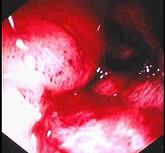

问题 男性,50岁。消瘦、乏力半年,间断性上腹胀痛伴黑便2周。发育正常,体形消瘦,贫血外貌,皮肤无黄染,腹平坦,腹肌软,上腹偏右压痛,肝脾肋缘下未触及。低张气钡双重造影示十二指肠降段肠壁僵硬,蠕动消失,肠腔不规则狭窄。胃镜检查如下图,下列正确的是 ( )

选项 A.十二指肠腺癌可能大 B.卓-艾综合征可能大 C.该病可导致黄疸 D.该病以中年人多见 E.该病首选手术治疗,无手术指征者可考虑放、化疗

答案 ACDE